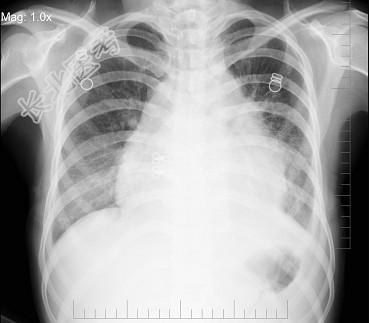

- 单项选择题女,24岁, 干咳1个月出现胸闷气急,活动时明显, 查体颈静脉显露,胸片如图, 最可能的诊断为 ( )

B、心包积液